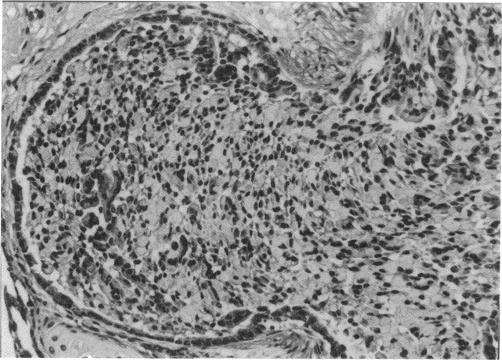

The morphologic changes induced in the lungs of rats and guinea pigs exposed to high concentrations of MIC vapor (100, 600, and 1000 ppm in the rat and 25, 125, 225, and 675 ppm in the guinea pig) for a short time (15 min) in a static exposure chamber were evaluated at varying postexposure periods (0, 1, 2, 4, and 16 hr). The 675 ppm-exposed guinea pigs were evaluated only immediately following removal from the chamber. Attention was primarily focused on the intrapulmonary conducting airways and the parenchyma (gas exchange region) of the lungs. The severity of morphologic changes observed by light microscopy was directly correlated with exposure concentration and time postexposure in both species. Specifically, degenerative changes were observed in the bronchial, bronchiolar, and alveolar epithelium in both species. Quantitative differences were observed; 100 ppm of MIC in the rat resulted in much less damage than did 125 ppm of MIC in the guinea pig. Morphologic evidence of sloughing of large sheets of conducting airway epithelium with fibrin buildup and increased mucus production resulted in plugging of major airways and atelectasis. These observations support the hypothesis that tissue hypoxia was a major contributing factor resulting in death.